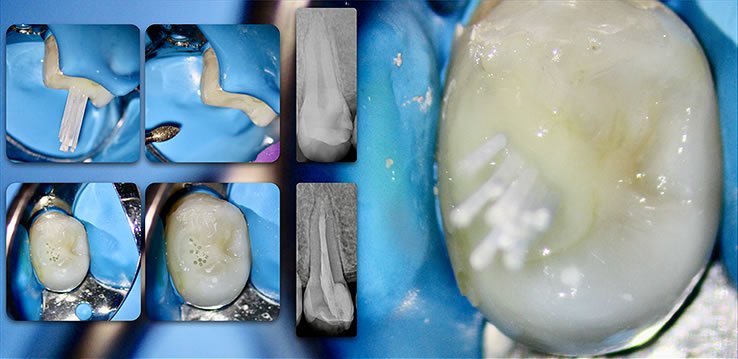

Retain 100% of remaining healthy tooth structure

- Biolight® DRILL-FREE adapts to all shaped canals, while conserving all remaining healthy tooth structure.

- There is no need to drill out portions of canals to accommodate post spaces.

- Easily place multi-posts in multiple canals as the post bends with the natural canal shape.

YES. Biolight® DRILL-FREE provides a solid, anatomical anchoring to remaining tooth structure. By arranging reinforcement towards the periphery of the canal walls, support of the core is improved. The concept is similar to how reinforcement steel rods and used in concrete structures, where many smaller rods are placed around the perimeter of the concrete. In addition, all risks associated with drilling are eliminated.

Biolight® DRILL-FREE posts are available in bundles of 4, 6, 9 and 12 strands. The post size is selected based on the width of the canal at the coronal area. Depending upon the canal width at the apical stop, a certain number of strands must be pushed to the stop. Both of the measurements are made with the assistance of a radiograph and the template that is included in the TRAINING KIT.

It is important to follow the steps in the instructional video. There is a procedure that will ensure predictable, bubble-free results (see 1:57 in the video).